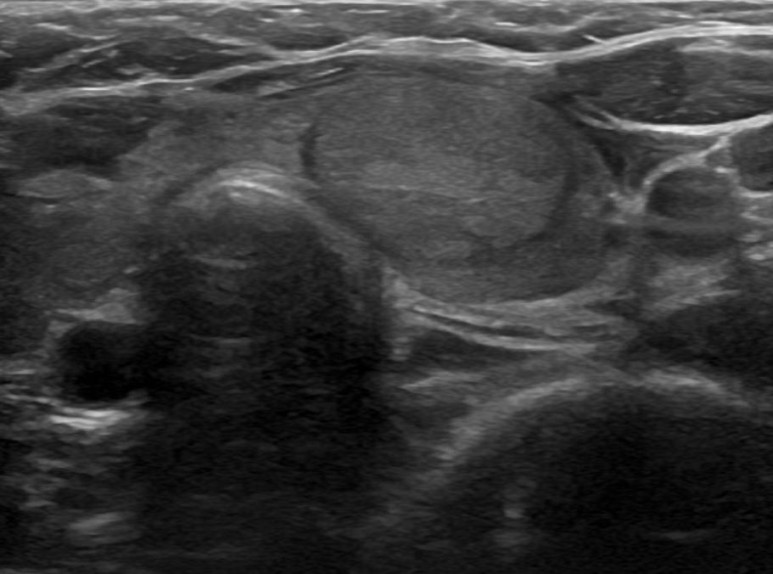

본원에서 갑상선세침흡인세포검사로 진단받은 갑상선암의 증례가 간혹 이어지는 목 이물감으로 인해 본원에 내원하신 30대 남성이었습니다.갑상선 초음파를 저희 병원에서 시행하였습니다.

갑상선의 좌우로 연결하는 잘록한 부위에 1.3센티미터 정도의 결절이 관찰되었습니다. 결절 내부에 석회 부분도 함께 세침 흡인 세포 검사를 실시했습니다.